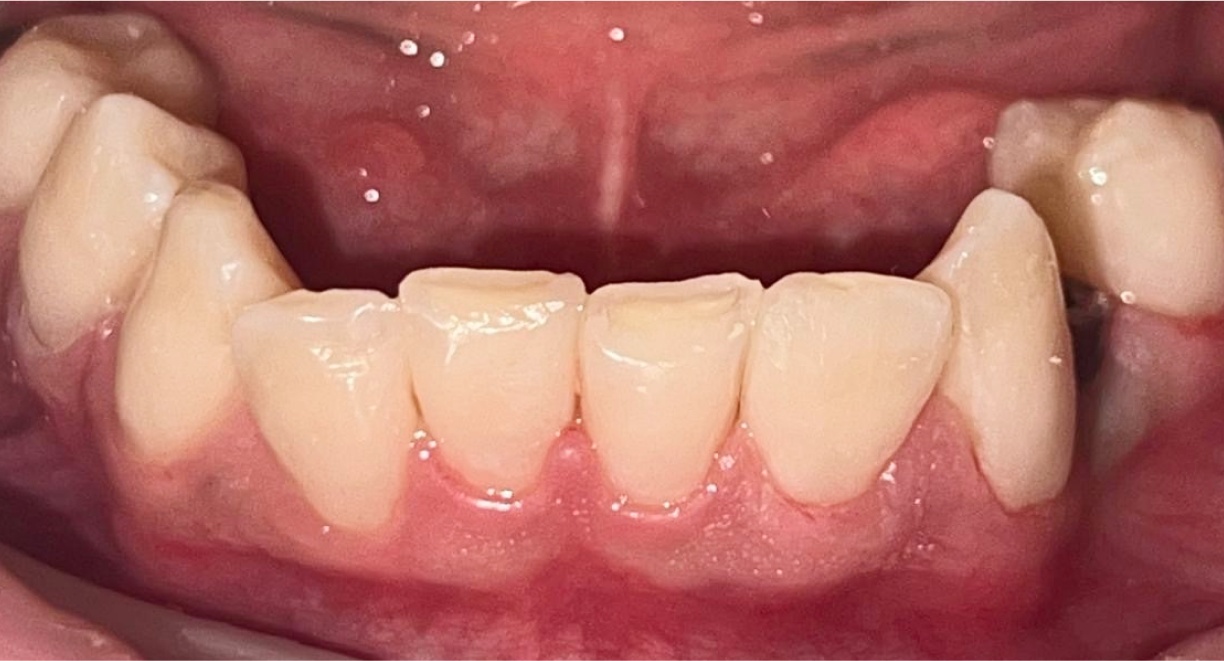

• Single-Tooth Dental Implant Placement + Dental Veneers for Full Smile Aesthetics

The patient was missing one tooth, and based on a detailed clinical evaluation, an individualized treatment plan was created. A titanium dental implant was placed into the jawbone, functioning as an artificial tooth root and providing a stable foundation for long-term restoration. After complete osseointegration, a custom-made zirconia crown was fabricated. It accurately replicates the natural tooth’s color, shape, and anatomy, restoring both chewing function and aesthetics. The neighbouring teeth are not affected during the treatment and remain intact. To ensure full smile aesthetics and a harmonious final result, dental veneers were also placed for the patient.